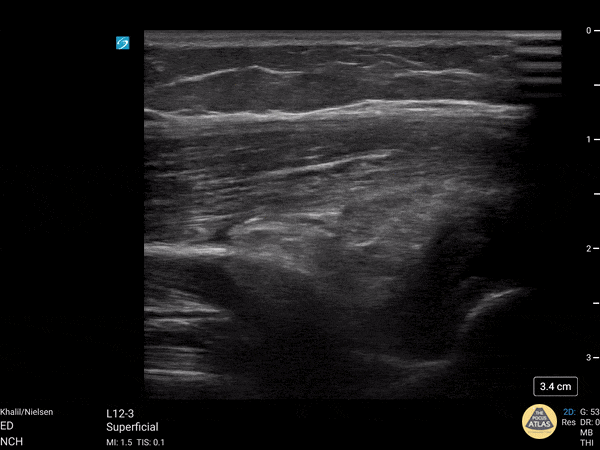

6 yo male with a supracondylar fracture, POCUS demonstrates a posterior fat pad Paul Khalil MD, Nicklaus Children's Hospital, @khalil3paul